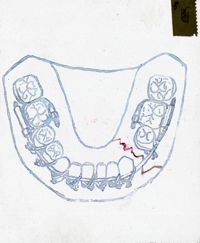

Image[Schéma des arcades dentaires, face vestibulaire.]